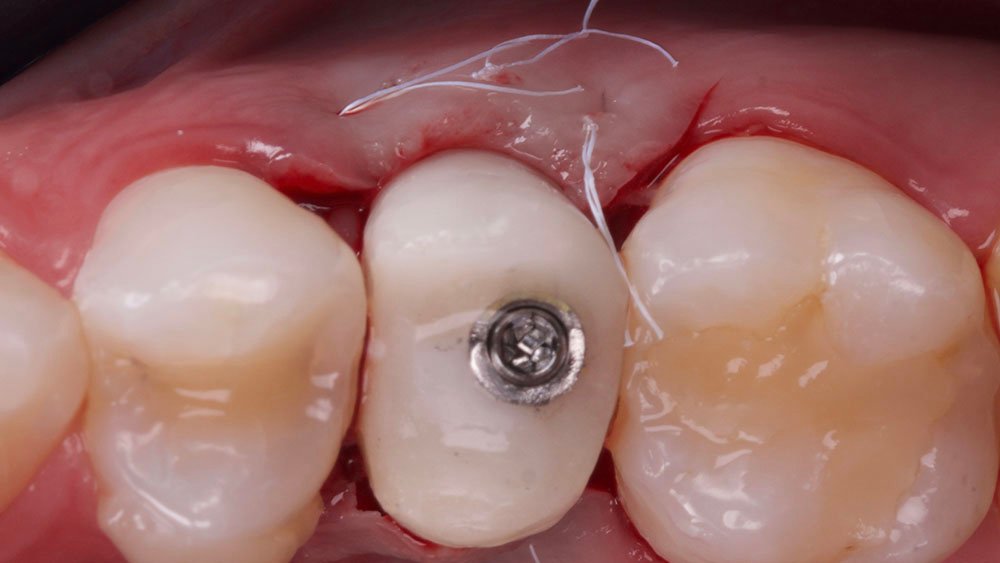

Confeccionou-se um dente provisório aparafusado com coifa de titânio 4,5 x 4 mm – Linha Ideale (Implacil De Bortoli, São Paulo-Brasil), sobre o Pilar Ideale 4,5 x 4 x 2,5 (Implacil De Bortoli, São Paulo-Brasil), apoiado no Implante Maestro 4 x 11 (Implacil De Bortoli, São Paulo-Brasil), obtendo um torque aproximado de 40N. E por fim, realizou-se a proservação e acompanhamento radiográfico.

O procedimento selecionado para esse relato de caso promoveu resultados satisfatórios e melhorou a estética. No término do procedimento cirúrgico, a paciente foi orientada a tomar uma cápsula de Amoxicilina 500 mg (EMS – Germed Farmacêutica, São Paulo- Brasil) a cada 8 horas por sete dias; um comprimido de Nimesulida 100 mg (Eurofarma Laboratórios S/A, São Paulo-Brasil) a cada 12 horas por três dias; e um comprimido de Dipirona 500 mg (Sanofi Medley Farmacêutica Ltda., São Paulo-Brasil) a cada 6 horas. Além disso, foi indicado à paciente que evitasse alimentos pastosos e pegajosos, que preferisse alimentos frios ou gelados e utilizasse bolsa de gelo no local.

No acompanhamento mensal realizou-se proservação e radiografias periapicais da região para verificar a cicatrização dos tecidos e integridade do implante. Após o período de três meses, foi cimentada uma coroa definitiva de zircônia monolítica.